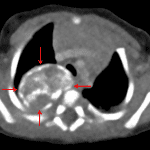

- Right posterior mediastinal mass measuring approximately 2.5 x 2.5 cm on the frontal view with associated rib splaying (right third and fourth ribs) and anterior displacement of the trachea

- Posterior mediastinal mass (thoracic neuroblastoma)

Right posterior mediastinal mass measuring approximately 2.5 x 2.5 cm on the frontal view with associated splaying of the right third and fourth ribs and anterior displacement of the trachea. Recommend chest CT for further evaluation.